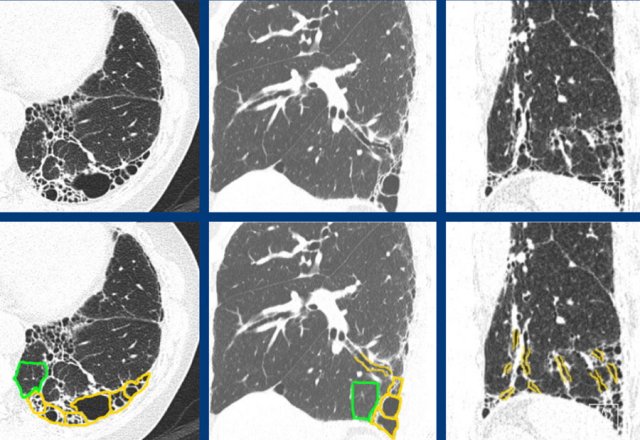

Severe fibrotic changes in a subpleural and basal dominant orientation, with extensive honeycombing, consistent with a UIP pattern due to rheumatoid arthritis (RA).

Rheumatoid arthritis can show multicompartment involvement and result in airways disease, pleural disease and interstitial lung disease, most commonly with a UIP pattern.